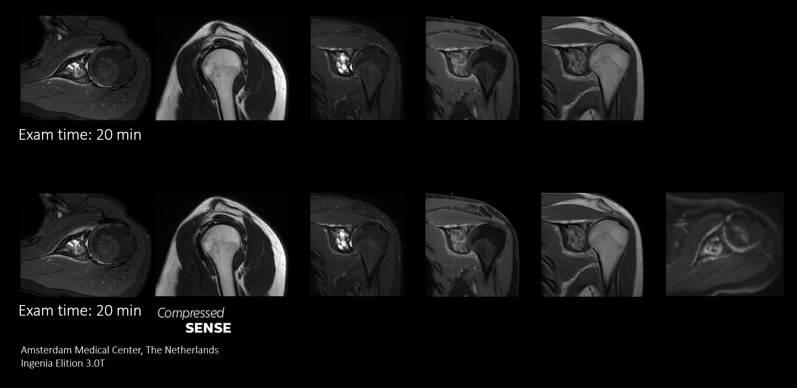

Compressed SENSE offre ai reparti RM la flessibilità necessaria per acquisire il maggior numero possibile di informazioni rilevanti nell'arco di tempo della scansione. Le sue velocità consentono di aggiungere sequenze funzionali e di routine supplementari per migliorare le informazioni diagnostiche.

In questo caso, la facoltà di aggiungere sequenze aggiuntive nel medesimo slot temporale permette di migliorare l'affidabilità diagnostica. Oltre alle sequenze TSE tradizionali, ora è possibile aggiungere una sequenza DWI funzionale all'interno dello stesso slot, così da disporre di ulteriori informazioni su cui basare la diagnosi.

Dal momento che la scansione più rapida con Compressed SENSE ci fa risparmiare tempo, possiamo aggiungere una sequenza per ottenere immagini di elevata qualità e stilare una diagnosi affidabile."

Dott. Sachi Fukushima, tecnico radiologo, Kurashiki Central Hospital (Giappone)